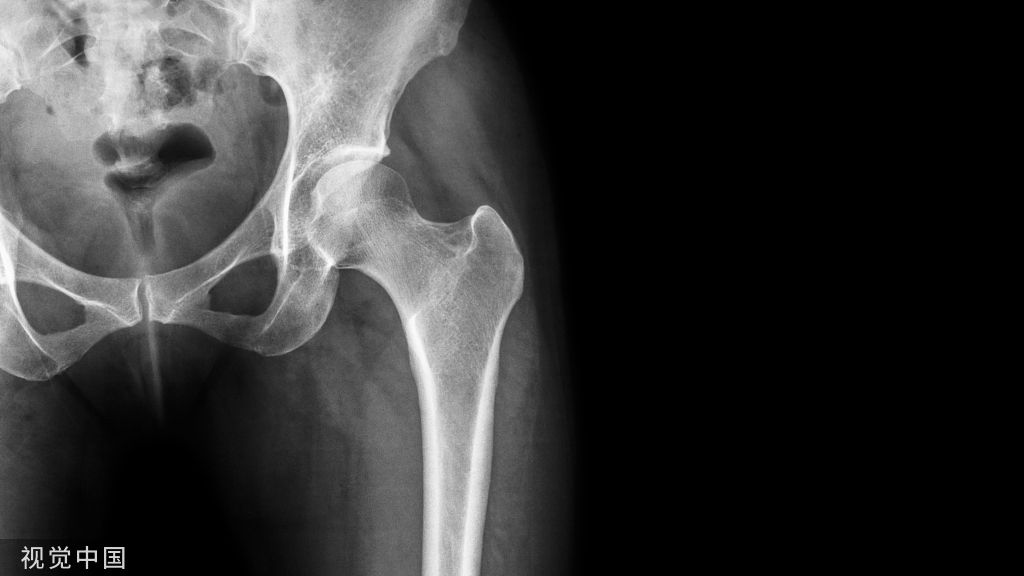

病例二患者,女,40岁主诉:摔伤致右膝部肿痛,活动受限。查体:右膝部肿胀,压痛,活动受限明显。下肢血运感觉正常,各趾可自主活动。辅助检查:X片示右髌骨骨折,骨折端分离

诊断:右髌骨骨折(下极骨折)